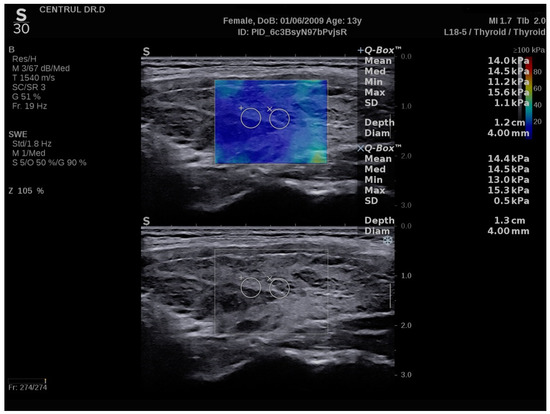

2.4. Conventional Ultrasound and Elastography Examination

3.2. SWE Measurements

3.3. SWE vs. Strain